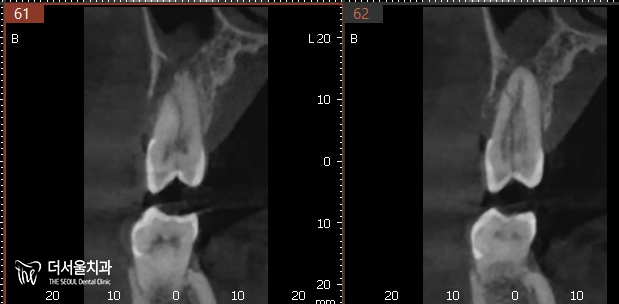

오른쪽에 단면을 보면,

수직으로 깊게 깨져있죠?

뿌리까지 파절되었기에

이를 살릴 수 없었습니다.

어떤 방향으로 봐도

뿌리까지 깊게 그어져있는 선을 볼 수 있습니다.